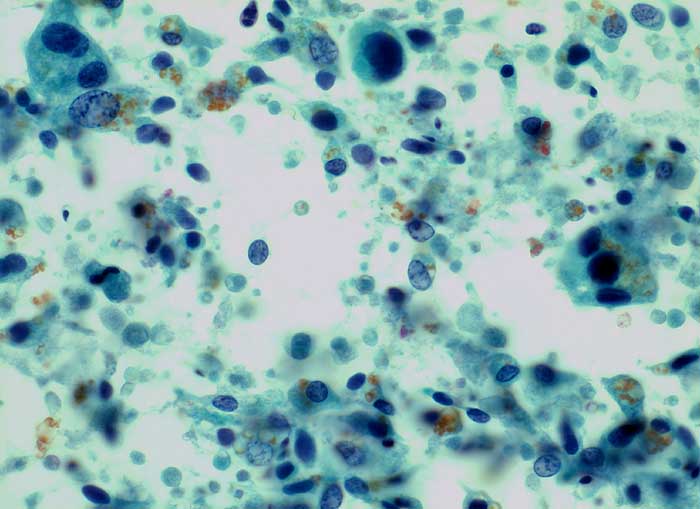

Die zytologische Diagnose des Prostatakarzinoms bereitet in der Regel keine grossen Schwierigkeiten. Die Karzinomzellen sind etwas grösser als normale Prostataepithelien. Die Kerne sind wenig grob strukturiert und ziemlich monomorph. Die Kern-Zytoplasma Relation ist erhöht. Nukleolen, die bereits bei 100 facher Vergrösserung gut sichtbar sind, stellen ein wichtiges Malignitätskriterium dar. Im Übrigen hängt das zytologische Bild von der Differenzierung des untersuchten Tumors ab.

Samenblasenepithelien können aufgrund ausgeprägter Atypien und manchmal erkennbaren Nukleolen mit Karzinomzellen verwechselt werden. Im Unterschied zu den Prostataepithelien enthält ihr Zytoplasma meist Lipofuszingranula.